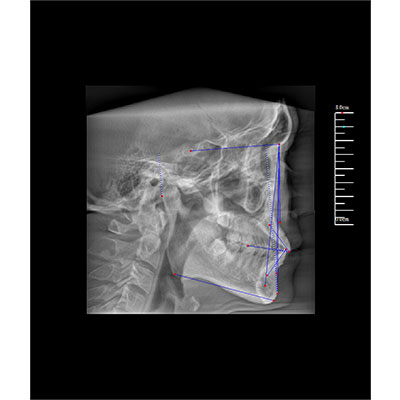

專有三維重建算法,可提供任意位置高清斷層影像。

可同時(shí)觀察軸向面、冠狀面和矢狀面圖像,方便臨床診斷。